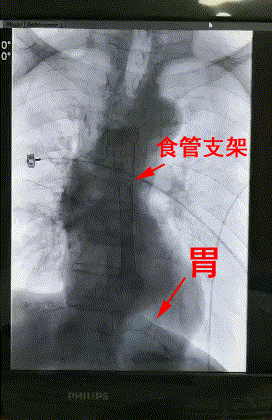

△術後DSA造影顯示:支架成功擴張食管狹窄端并封閉瘘口。

3月28日上午,楊阿姨被送進了介入手術室,李旭丹主任等專家根據術前方案上台施術,先采用飛利浦DSA開展食道造影,明确食道狹窄端及瘘口位置,後經導絲引入食管支架釋放于準确位置。DSA顯示支架成功擴張食管狹窄端并封閉瘘口,順利完成手術。

術後患者無不良反應,生命體征平穩,24小時後能夠進食。楊阿姨及其家屬非常感激。